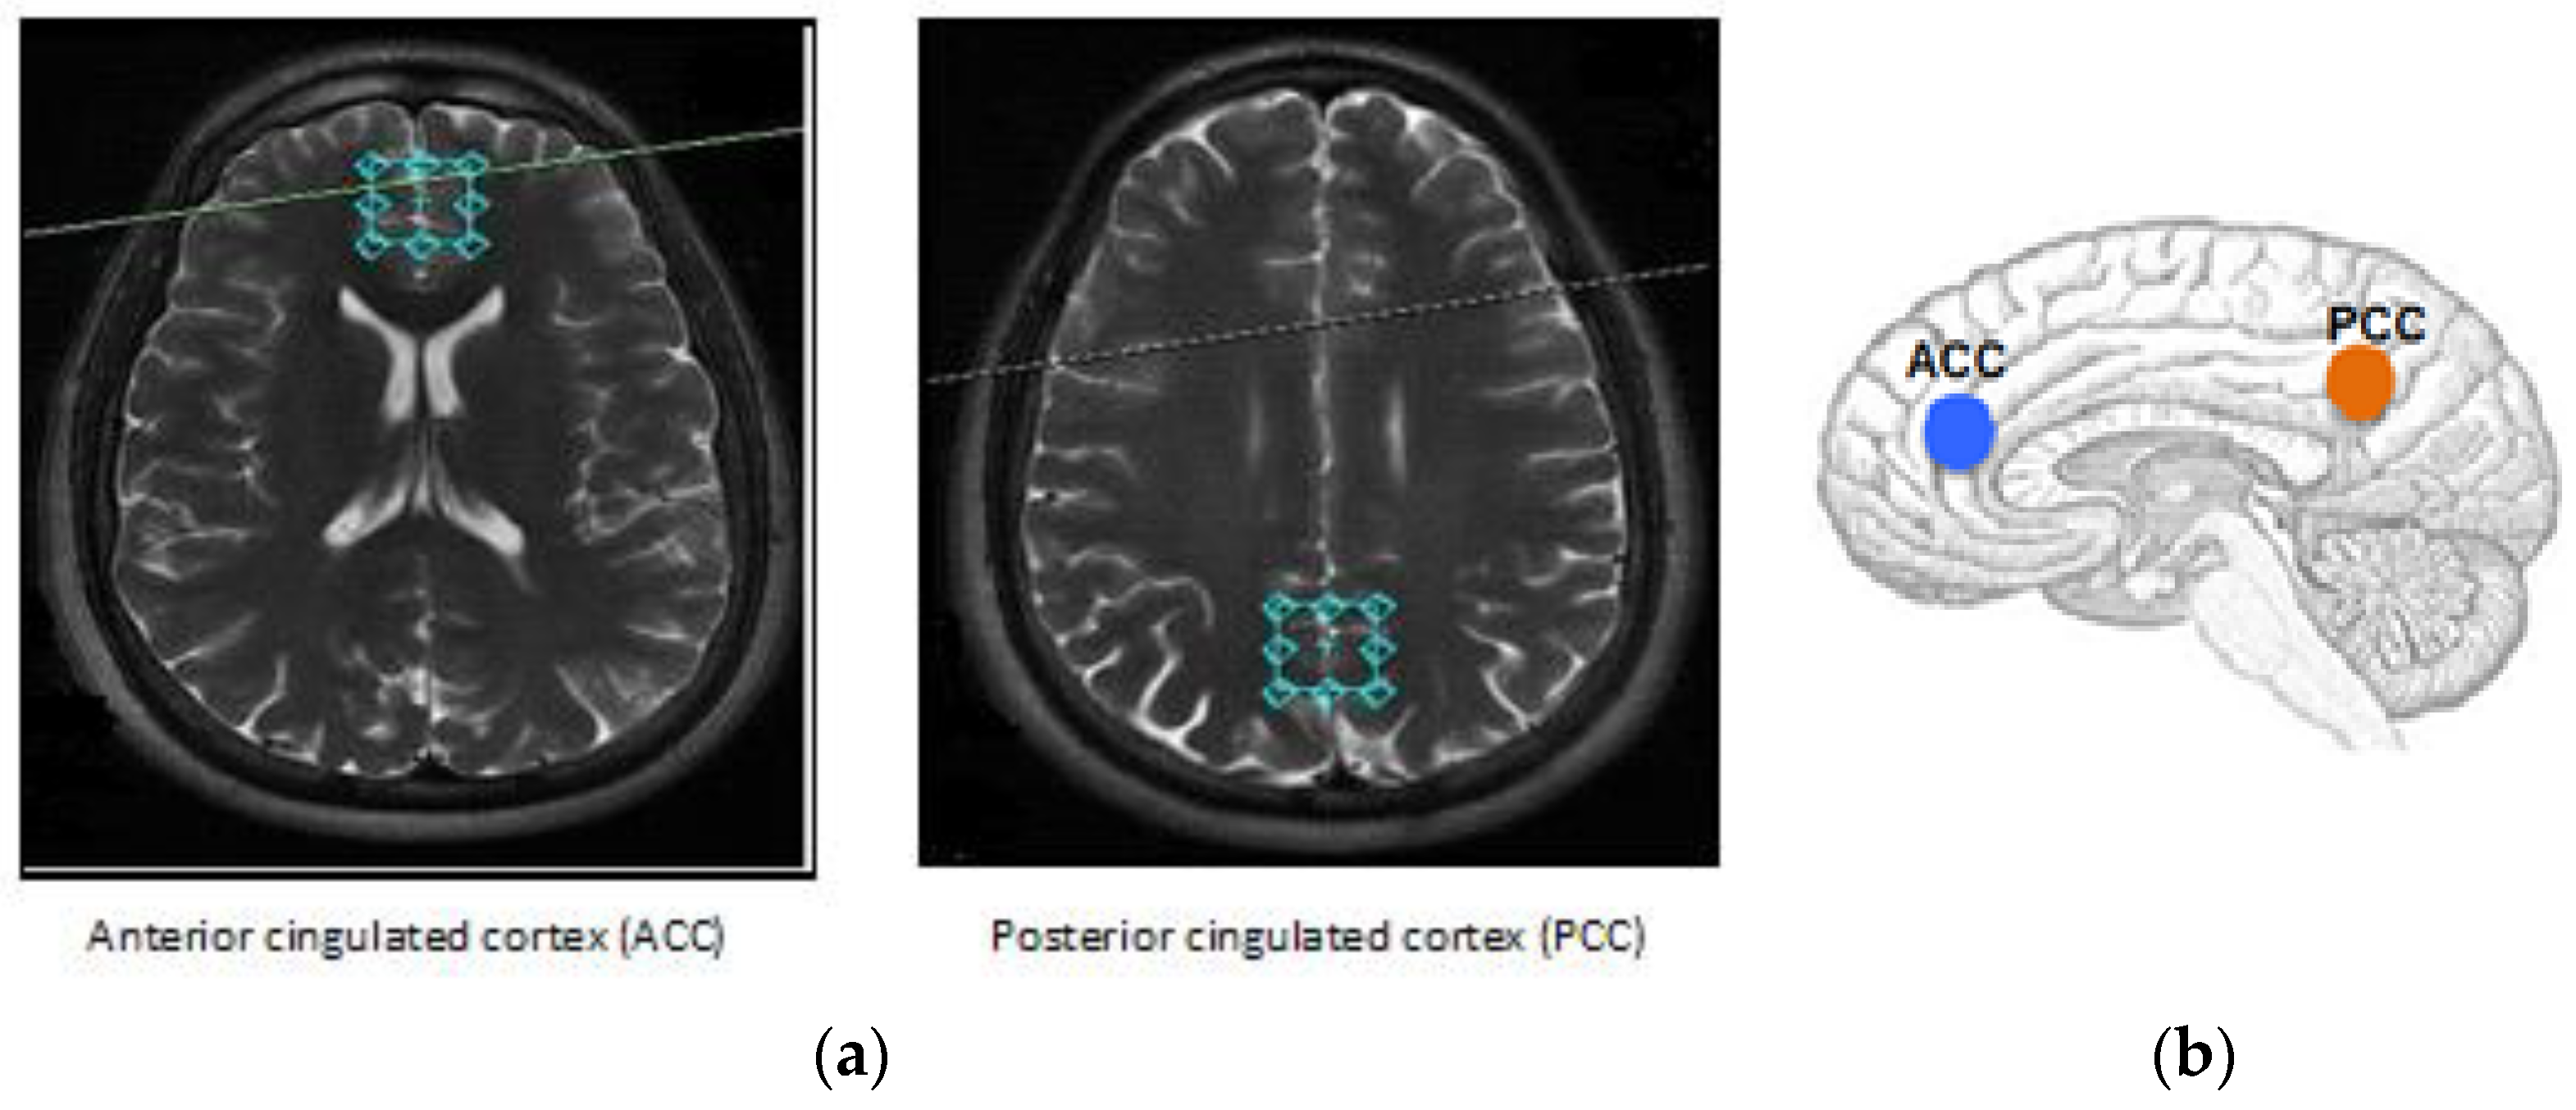

During data acquisition, the same experienced neuroradiologist, blind to the clinical data, placed the voxels (2 × 2 × 2 cm3) at the ACC and PCC (see Figure 1). The ASD group had an abnormal pattern of metabolites in the ACC with a significant increase in glutamate (12.10 ± 3.92 mM; p = 0.02), as well as a significant decrease in N-acetylaspartyl-glutamate (0.41 ± 0.27 mM; p = 0.02), compared to the typical development (TD) group (see Table 2).

All subjects underwent an MRI and 1H-MRS using a 3T Signa-HD MR scanner (GE Healthcare, Waukesha, WI, USA). T2-weighted images were used for positioning the volumes of interest (VOIs). The single voxel acquisition used a spin-echo sequence recorded within the following parameters: TE = 23 ms, TR = 1070 ms, NEX = 2, flip angle = 90°, and 256 acquisitions with the point-resolved spectroscopy (PRESS) technique. During data acquisition, the same experienced neuroradiologist, blind to the clinical data, placed the voxels (2 × 2 × 2 cm3) at the ACC and PCC. The main metabolite resonances were limited to 2.02 ppm for NAA, 2.04 ppm for NAAG, 3.03 ppm for Cr, 3.20 ppm for Cho, 3.55 ppm for mI, and, 3.77 ppm for Glu. We used a TE of 23 ms, as it is known that myoinositol can be readily detected in a short TE using 1H-MRS spectra of the brain due to its high concentration of (4–8) mM [71]. Each voxel was positioned so as to exclude contamination of signal from the skull and subcutaneous fat. Morphological examination enabled us to exclude other pathologies, such as congenital abnormalities, lesions in cerebral palsy, tumors, and hydrocephalus.

Figure 1 demonstrates that the volume of interest (VOI) was located in the ACC and PCC regions, where we collected data on metabolites from two subject groups, i.e., ASD and TD. The spectra for each location were investigated separately and averaged. The results were processed with LCModel 6.3 to obtain absolute concentration estimates for the following metabolites in each location in each subject: Cr, NAA, NAA + NAAG, NAAG, Cho, mI, Glx, and Glu¸ considering the use of ratios does not necessarily assume one metabolite to be constant [73]. Furthermore, the ratios account for all non-metabolite-specific differences, and therefore can be reasonably compared across all participants scanned at the same institution with the same protocol.